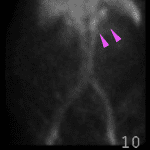

Age: 88

Sex: Female

Indication: GI bleed

Radiotracer: Tc99m labeled RBCs

Sample ReportEvidence of active GI bleeding with the likely origin from the stomach.